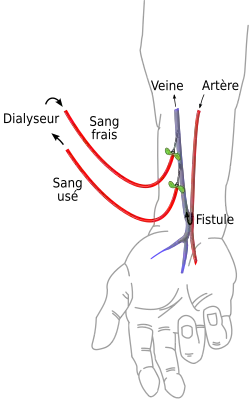

Fistule artério-veineuse

La fistule artério-veineuse est volontairement fabriquée par le chirurgien qui abouche une veine du bras dans une artère, ce qui a pour effet d'augmenter le débit à ce niveau (chute des résistances par shunt du réseau distal capillaire) et d'obtenir une dilatation veineuse importante et une augmentation de la résistance de la paroi de la veine (elle prend un aspect d'artère), pour permettre la pose ponctuelle de circuits de circulation extra-corporelle lors d'un traitement par hémodialyse. La fistule possède l'avantage sur le cathéter (posé obligatoirement sur une grosse veine centrale) de permettre la cicatrisation entre les séances – et par conséquent moins d'entrée de germes.

Certaines fistules artério-veineuses sont spontanées et selon leur importance elles peuvent entraîner des troubles circulatoires, voire une insuffisance cardiaque à haut débit.